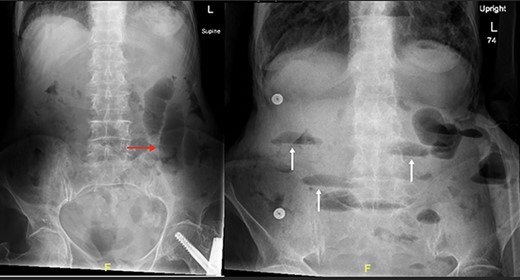

The patient’s lab results revealed leukocytosis of (12.40 m/mm3), and C-reactive protein of (28 mg/l). Abdominal X-ray demonstrated distended small bowel loops with multiple air fluid levels (Fig. 1). Moreover, CT revealed right sided obturator foramen hernia containing a segment of distal ileum causing high-grade small bowel obstruction, which reached up to 4 cm (Fig. 2). The CT also showed extensive bronchiectasis and consolidation with mucus plugging in the lung base.

Axial (a–c) and Coronal (d) contrast-enhanced reformatted CT image of the abdomen shows distal ileal loop segment protrudes through the right obturator foramen with the herniated segment trapped between the right obturator externus and pectineus muscles (blue arrow), there is proximal upstream dilated small bowel loops (red arrows). In keeping with high-grade small bowel obstruction due to strangulated obturator hernia.